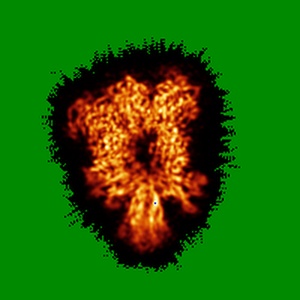

Cryo-EM structure of murine Thrombopoietin receptor ectodomain in complex with Tpo

Sample: 2:1 complex of the mouse thrombopoietin receptor ectodomain and mouse thrombopoietin

Cryo-EM structure of the extracellular domain of murine Thrombopoietin Receptor in complex with Thrombopoietin.